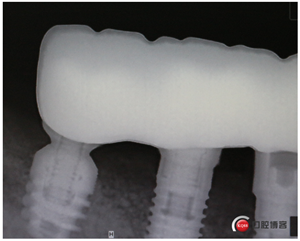

同期植入植體。

縫合,快!忒快了,二十分鐘搞定。不要懷疑,這是真的,參加過我的學(xué)習(xí)班的老師都看過我的很多視頻,超級安全、超級快。

說書的一張嘴,唱戲的跑斷腿,轉(zhuǎn)眼間半年過去了,見證時刻的奇跡到了!